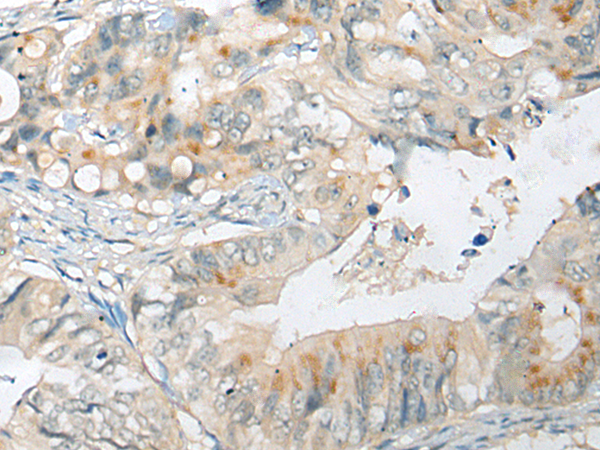

IHC (Immunohistochemistry)

(The image on the left is immunohistochemistry of paraffin-embedded Human liver cancer tissue using 46469(CELSR1 Antibody) at dilution 1/30, on the right is treated with synthetic peptide. (Original magnification: x200))